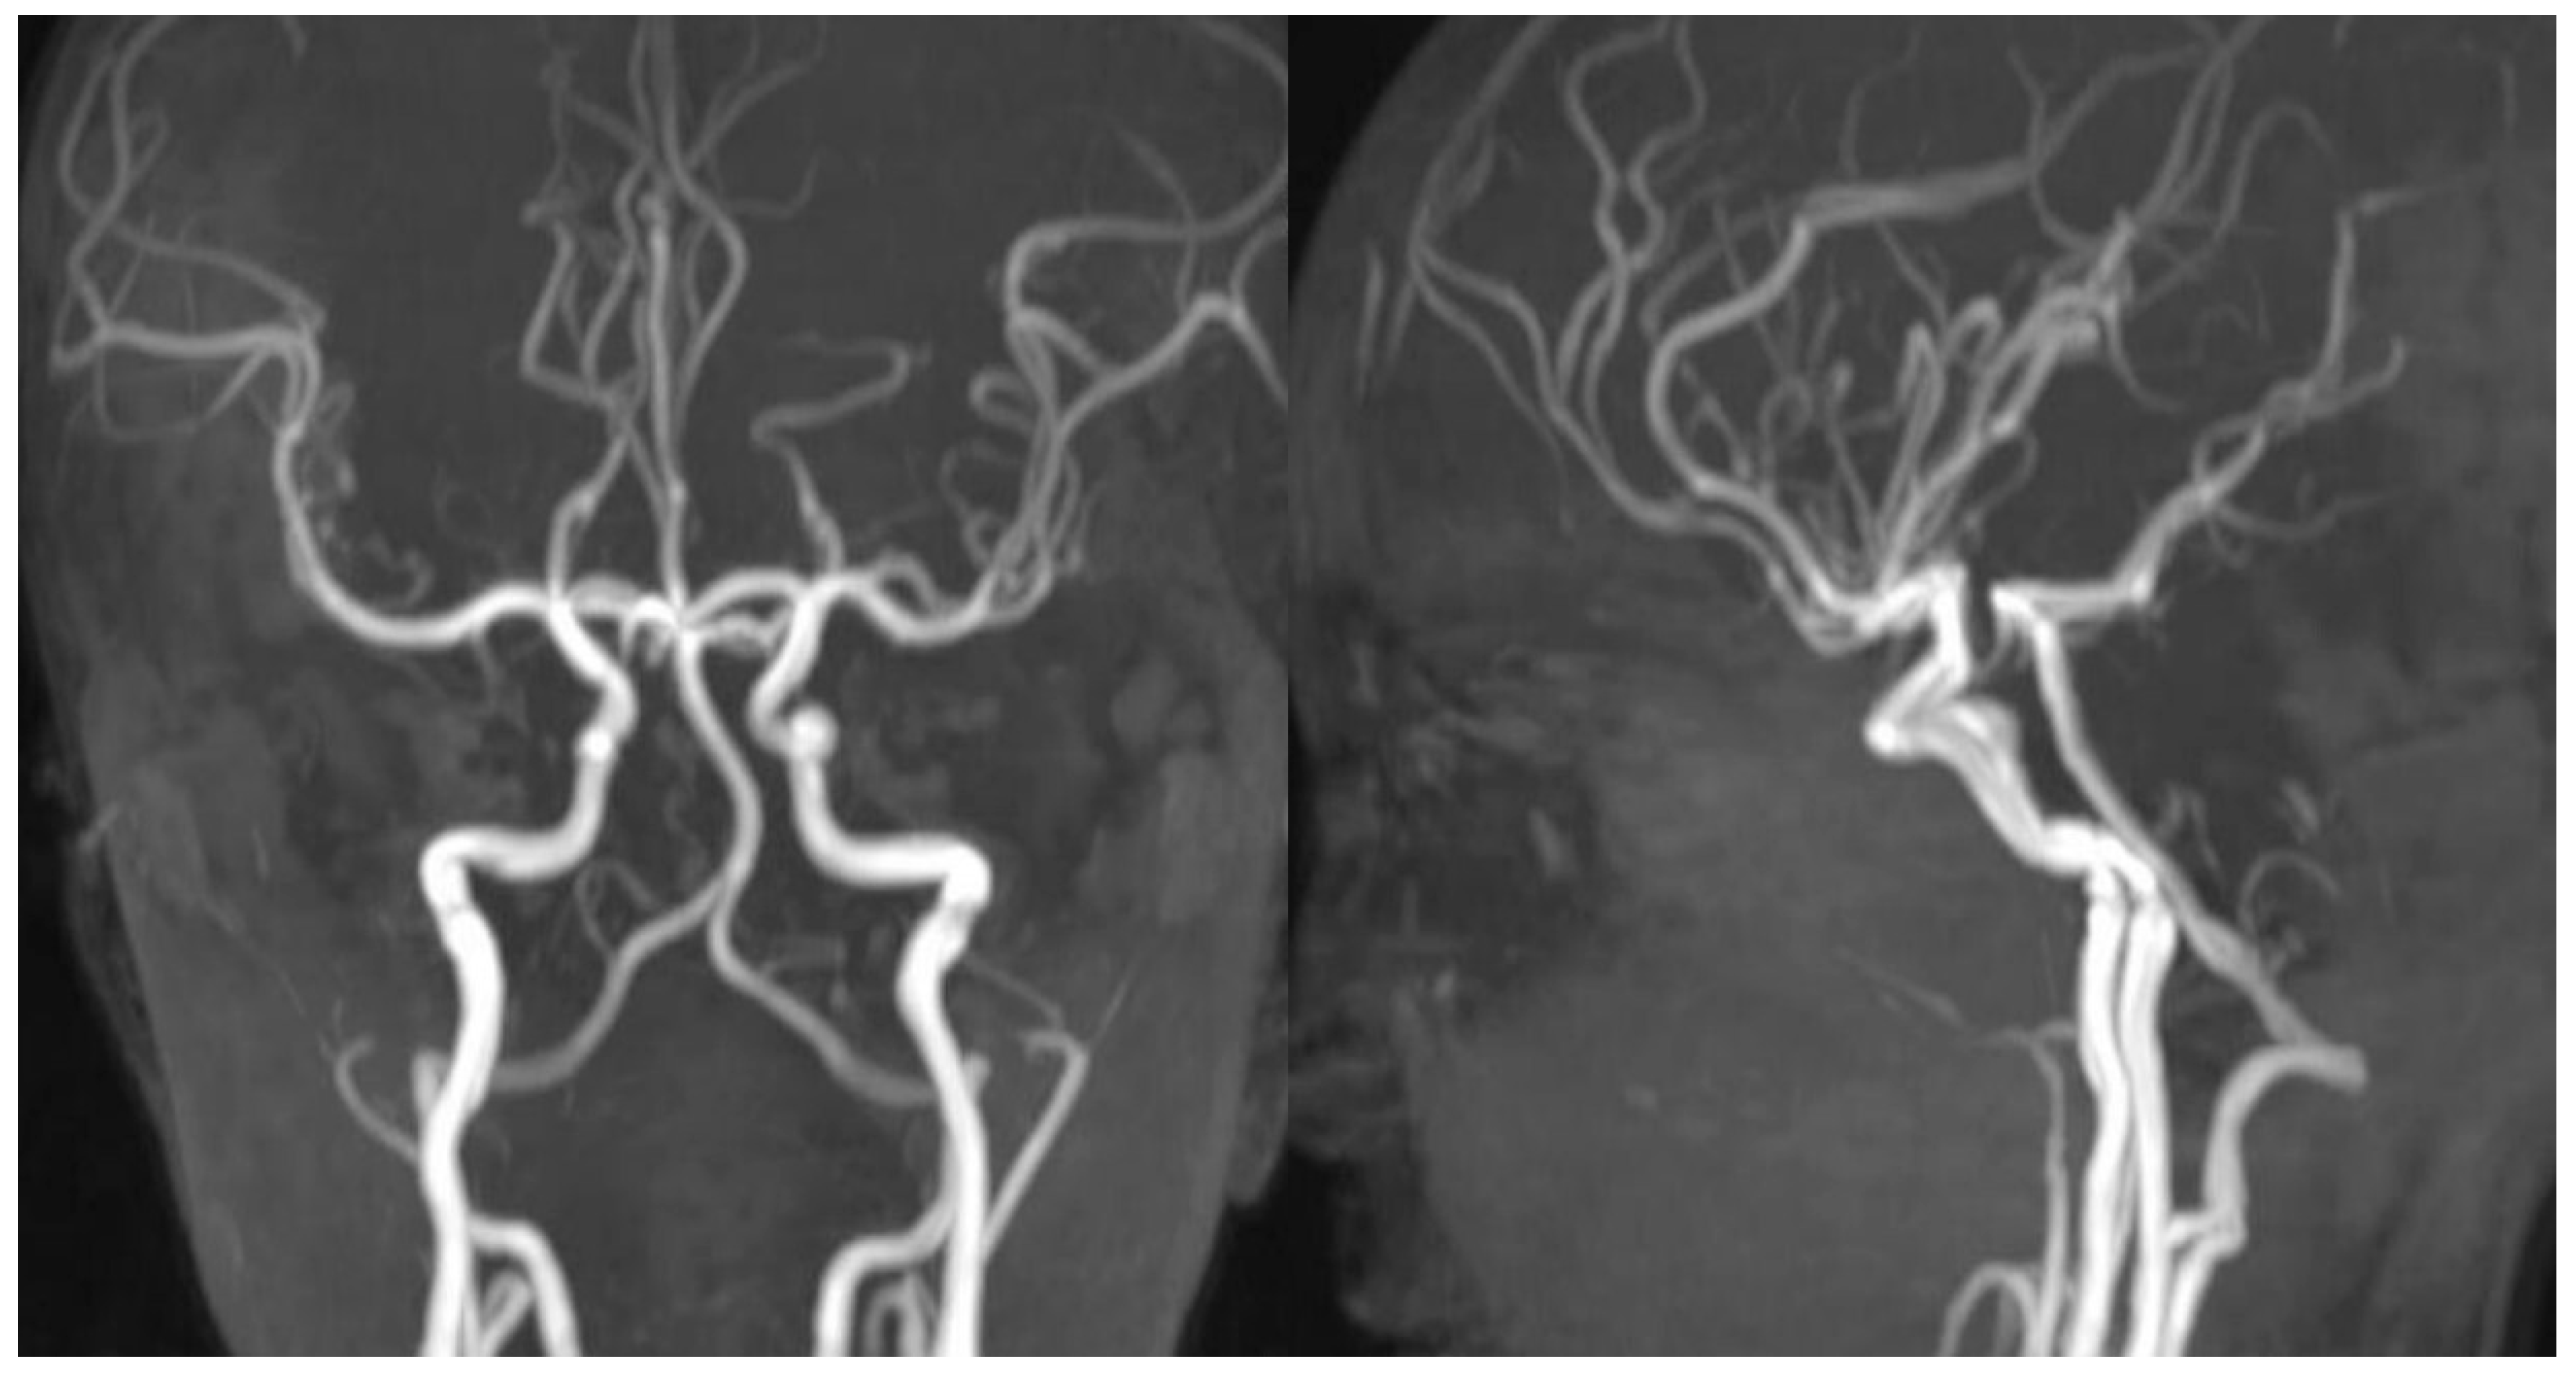

The patient had no significant past medical history, and laboratory evaluations were within normal limits. Cranial MR angiography and MR venography were performed; however, no vascular malformation was identified on either imaging modality (Figure 2 and Figure 3).

Figure 2. Post-hemorrhagic MR angiography after the initial intracerebral event.